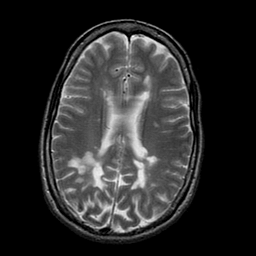

Multiple Sclerosis, MR Study mr-t2 -- Slice #14

[Home][Help][Clinical] Slice 14